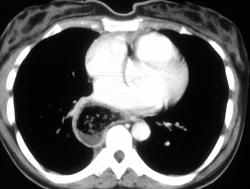

Leiomyoma Esophagus